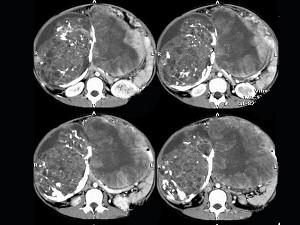

问题 女,43岁,发现盆腔包块3年,排尿困难6日,影像检查如图,最可能的诊断是()

选项 A.腹腔脂肪肉瘤 B.腹腔恶性间质瘤 C.腹腔畸胎瘤 D.腹腔畸胎瘤伴卵巢内胚窦瘤 E.卵巢内胚窦瘤

答案 D